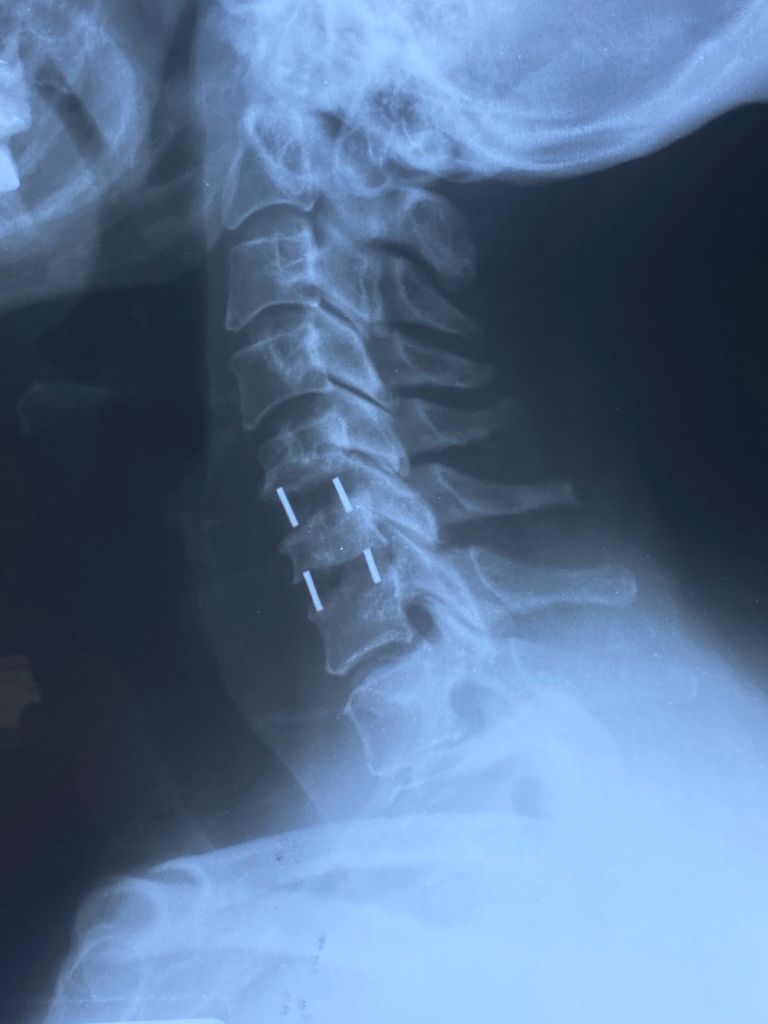

Fotos y videos

Estimulación magnética transcraneal para el tratamiento de ansiedad y depresión por la pandemia así como deterioro cognitivo

04/01/2022